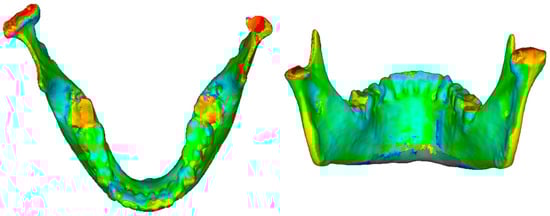

2.4.2. D Qualitative Assessment

3.1. D Qualitative Assessment